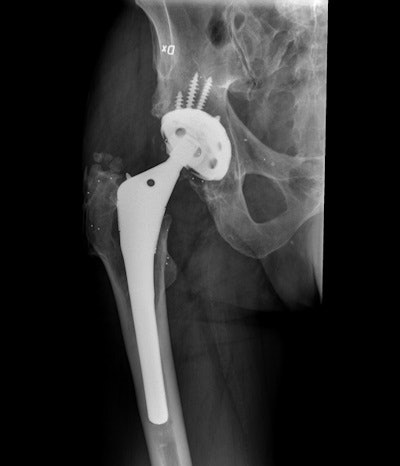

High resolution x-ray shows prosthetic hip implant. The white dots are the tantalum markers that will create polygons between bone and implant. All images courtesy of Dr. Maziar Mohaddes, PhD.

The technique can only be deployed if during hip surgery tantalum markers are placed in the implant. Ten markers are inserted in the femoral bone, 10 in the plastic hip socket, and 10 in the pelvic bone. Soon after surgery, the patient is x-rayed, this against a reference plate and with two beams so that he or she can be correlated with the room. The markers create polygons inside the bone and in the implant. These polygons are imaged periodically so that any movement between the bone markers and prosthesis markers can be visualized. This movement can then be compared postoperatively from one exam to another over a period of time.